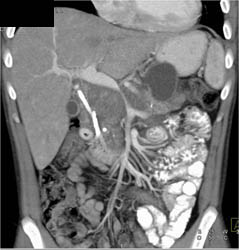

Pancreatic Cancer Encases the PV/SMV